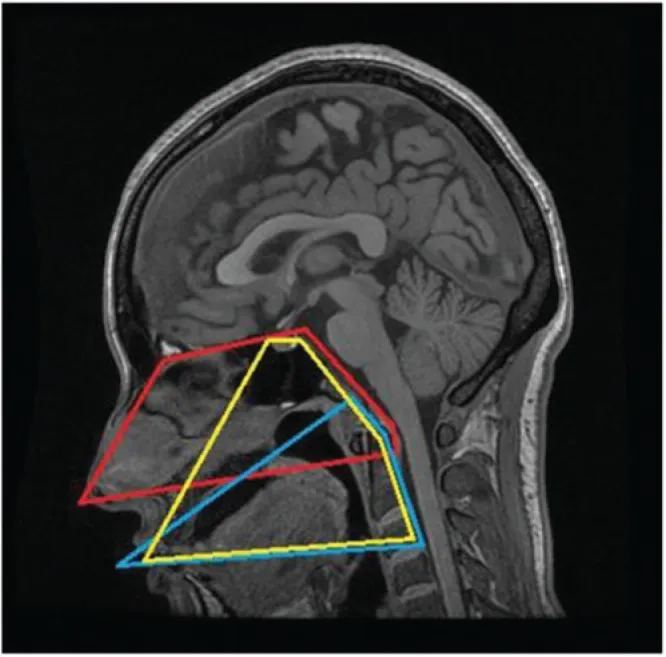

图示:在MRI的矢状中位面上每种方法的局限性。红线表示EEA,蓝线TOA,黄线TO-TPA。TO-TPA的手术视野在上部区域与EEA的手术视野重叠,在下部区域与TOA的手术视野重叠。

经口-经腭入路(TO-TPA):其上界可达前颅底,并能够显露至视交叉区域;其下界可抵达第三颈椎(C3)椎体水平。这使得该入路特别适用于处理从斜坡延伸至上颈段的病变。

内镜经鼻入路(EEA):其上界同样可达前颅底,具体为额窦后壁;但其下界受硬腭的阻挡,通常限于第一颈椎(C1)水平。因此,对于向颅颈交界(CVJ)以下延伸的肿瘤,EEA的视野和操作会受到明显限制。